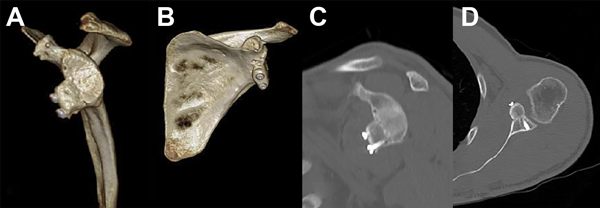

Respecto de los resultados imagenológicos (fig. 4), el injerto óseo consolidó en todos los pacientes. Según los criterios de Burkhart15 y Kany16, en la vista axial, ocho de los diez injertos fueron colocados dentro del rango objetivo (-5 a +3 mm). En contraste, un injerto quedó lateralizado y uno, medializado.

Figura 4: Tomografía de control a los tres meses de la cirugía de revisión con injerto de cresta ilíaca. A) Reconstrucción 3D vista lateral. B) Reconstrucción 3D vista anterior. C) Corte parasagital. D) Corte axial.